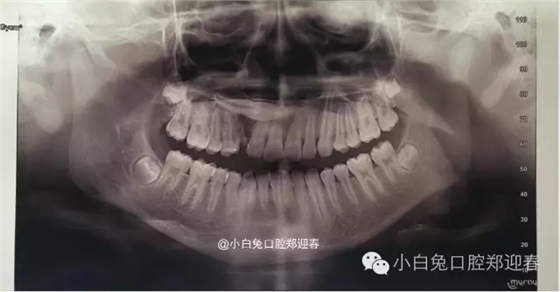

術(shù)前全景片

全景片顯示:53滯留,13橫位阻生,但是全景片反映不出真實的阻生尖牙的解剖位置,因此要借助CT進行定位。